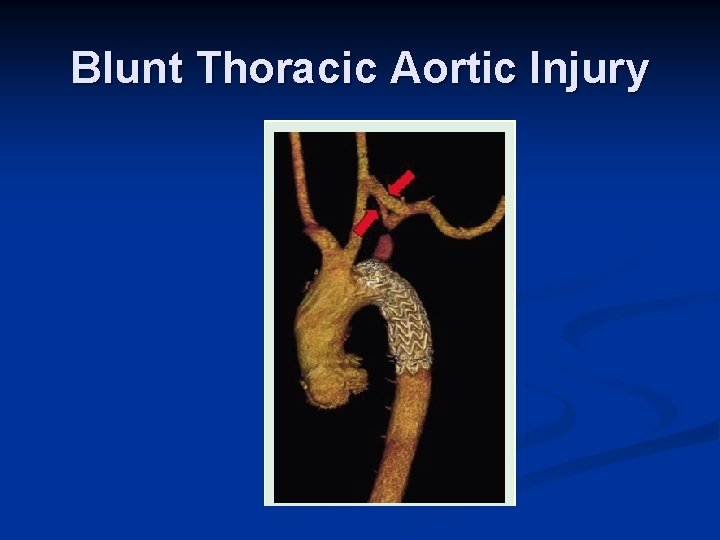

Role of Interventional Radiology n Embolization Spleen n Liver n Pelvis n n Angioplasty + Stent n n Renal artery dissection Stent n Thoracic aortic injuries

Blunt Thoracic Aortic Injury